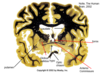

occipital lobe lesion. alsmost superimposable field defects. left occipital lobe causing right sided visual field defect.

AVM malformation in left occipital lobe causing right sided visual field defect